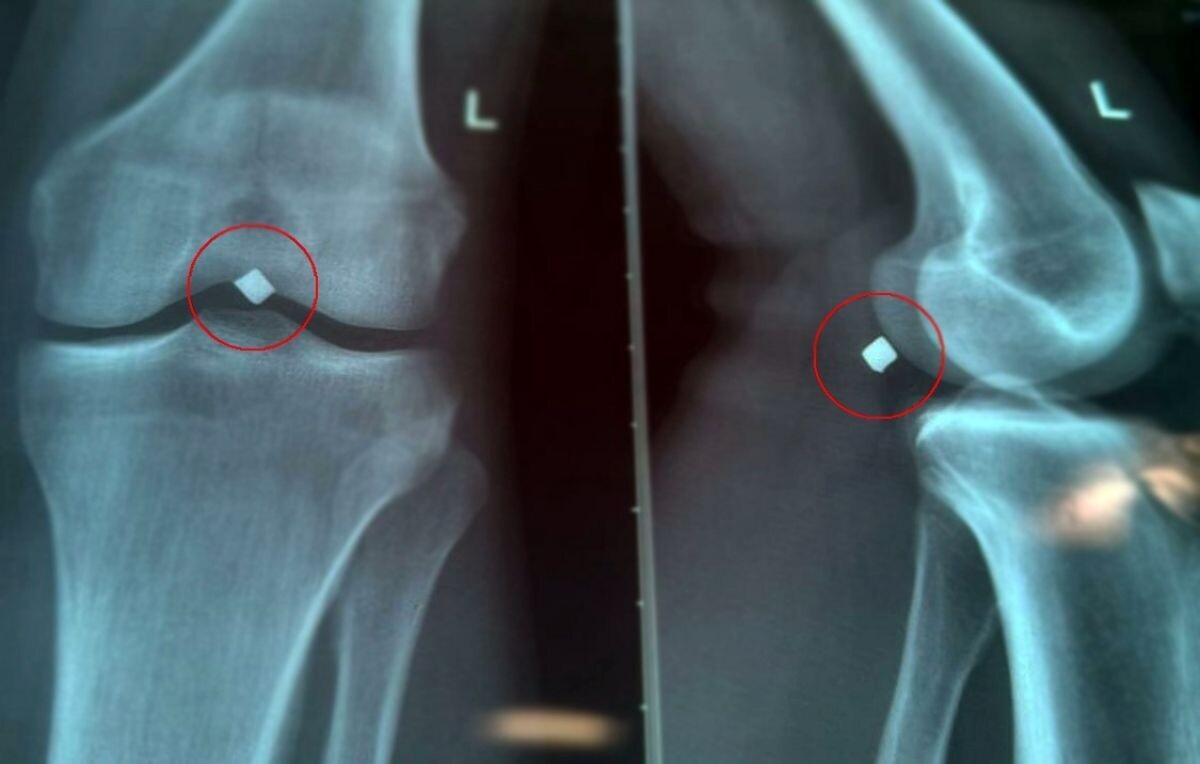

Один из пациентов - 22-летний парень. В июне 2025 года он получил серьезное ранение осколком - пробил надколенник насквозь, прошел через полость коленного сустава и застрял всего в паре миллиметров от крупного сосудисто-нервного пучка нижней конечности. Пациента беспокоили постоянные боли в области инородного тела. Осколок оказывал давление на нерв, вызывал стойкий дискомфорт и нарушение функции левой нижней конечности.

По словам сердечно-сосудистого хирурга Вячеслава Карпова, выяснилось, что осколок лежал прямо на стенке подколенной вены и практически пролабировал ее, создавая прямую угрозу жизнеугрожающего кровотечения. Операция прошла успешно, осколок был благополучно и аккуратно удален.